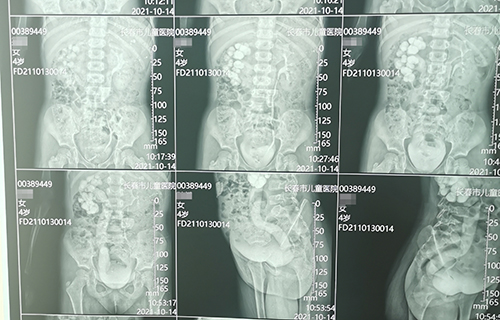

术前准备完毕。10月15日,栾志勇主任、谢方达副主任为佳佳行输尿管远端狭窄微创手术,在其肚脐周围打了3个直径5mm的小孔,在腹腔镜下顺利实施了输尿管膀胱再植。手术用时仅为3小时,出血量也比较少。

佳佳复查彩超,手术效果良好,达到出院标准。10月22日,佳佳就可以回家了。截止到目前,此类微创手术已完成8例。